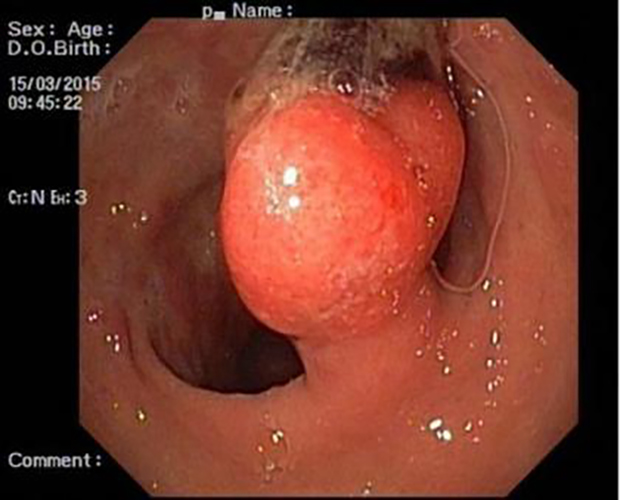

胃息肉圖片

增生性胃息肉

增生型胃息肉

早期良性胃息肉